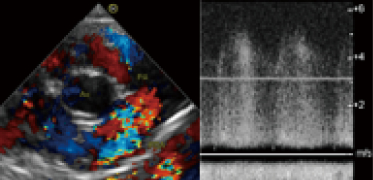

上)生まれつき心臓に異常がある犬の動脈管開存症の超音波画像です。

開胸手術で異常な血管である動脈管を結紮し、現在は完治して健康な犬と同じように元気に過ごしています。

※動脈管開存症の無治療での1年生存率は50%以下です。